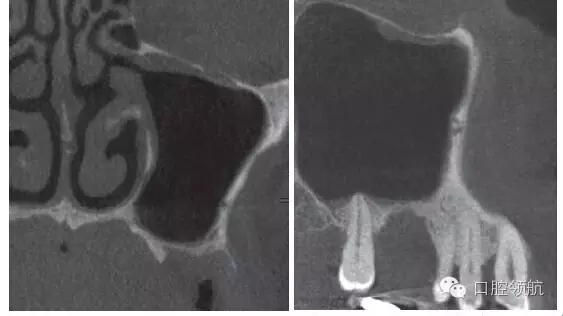

拔除(左上第六顆牙)后,抗生素(500mg)口服1周。術后4周的CBCT顯示,上頜竇黏膜增厚明顯改善(圖3)。

圖3 拔牙后4周,上頜竇黏膜增厚消失,但仍有殘留牙槽窩。